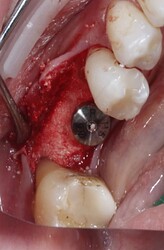

(buccal wall thickness is adequate right after implant)

I also noticed at implant placement i see 2 occlusal defects mesial and distal of the implant (most likely indicating mesial and distal root of previously extraction). which indicated the ridge is not fully ossified or calcified. i wonder if during osteotomy you felt soft bone instead of the usually hard mandibular bone. i think at implant placement you should have grafted. the occlusal is kind of flat, as if you did some occlusal reduction of some kind.

your buccal flap is also too deep which exposed the buccal plate and cause further resorption. at edentulous sites i usually only flap occlusal and stop at the buccal occlusal line angle of the ridge. avoiding exposing buccal plate to avoid devascularizing the buccal plate. every time you flap you will lose minimum of 0.5-1mm of bone. that’s research proven by perio.